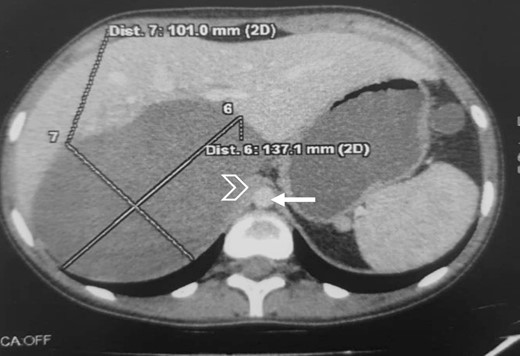

The CT scan incidentally revealed an adrenal incidentaloma in the form of a large right retroperitoneal mass measuring 137 × 101 × 114 mm3, occupying the adrenal cavity, oval, well defined, with regular contours, hypodense, containing areas of fluid density and others of tissue density without significant contrast enhancement, with a wall showing focal thickening of tissue density with low contrast uptake (Fig. 1).

Large right retroperitoneal mass, hypodense, oval, well defined, with regular contours (arrow: aorta; arrowhead: IVC).